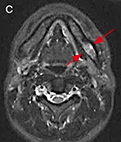

c:MRI、STIR

図❷ CT画像では、左側下顎骨体部と左側鎖骨胸骨端の骨髄にhigh density areaを認める。MRI画像で同部の骨髄は、STIRで高信号を呈する

画像所見:パノラマX線写真では、67部の下顎骨体部に淡いすりガラス様のX線不透過像が認められた(図❶)。CT画像では、左側下顎骨体部の骨髄に high density area を認め、また、左側鎖骨胸骨端にも同様の像が認められた。MRI画像で同部の骨髄は、T1W1で低信号、STIRで高信号を呈していた(図❷)。